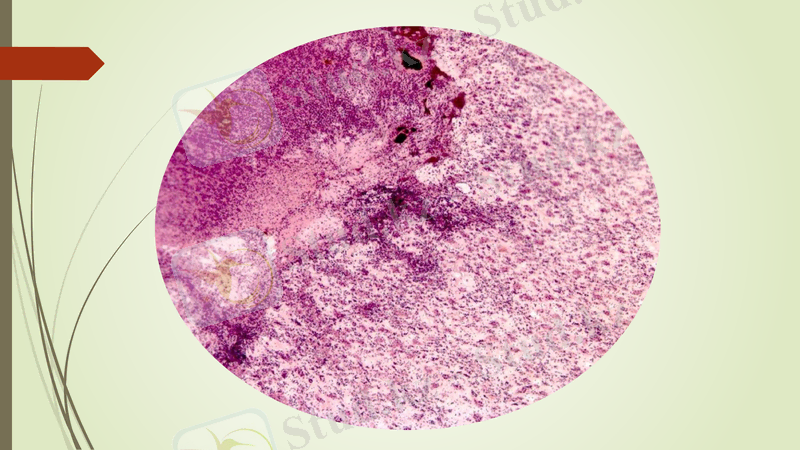

Май эмболиясы

жіліктер сынған кезде, тері асты майлары езілгенде, дене күйгенде, кейде құрамында май бар дөрілерді қанға кездейсоқ дарытқанда немесе қанның физикалық-химиялық қасиетгерінің өзгеруі нәтижесінде оның құрамында май тамшыларының түзілуіне байланысты пайда болады. Май тамшылары бірінші кезекте өкпе капиллярларын тығындап қояды. Өкпе ка-пиллярларының 75% маймен толғанда қанның өкпеден жүрекке өту мүмкіншілігі болмай жедел асфиксия (ауа жетіспеушілігі) дамып, ауру мал тез өліп қалады.